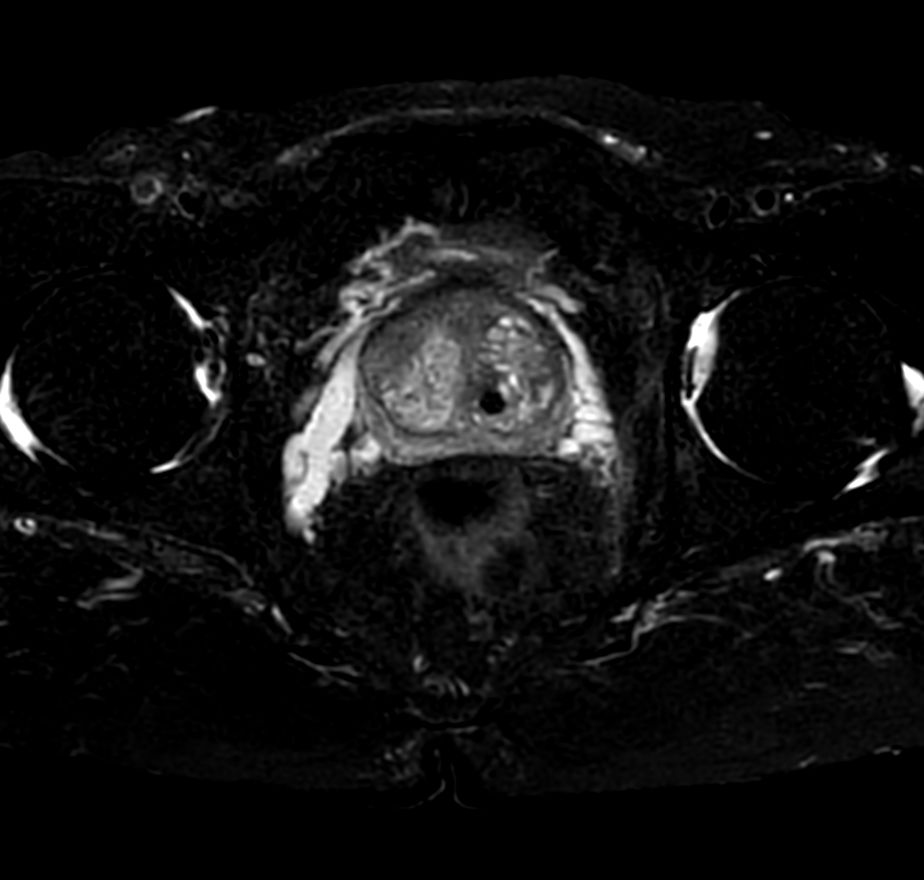

T1w FFE mDIXON XD- Compressed SENSE